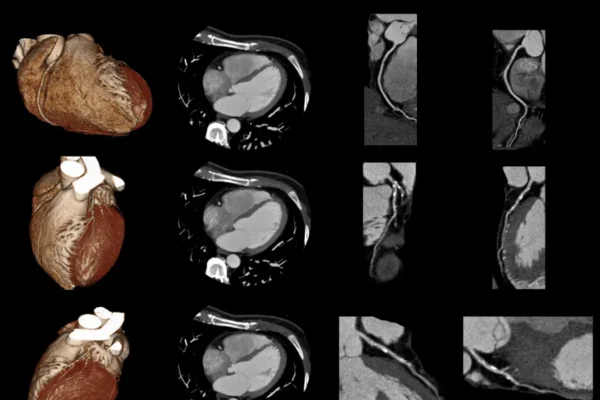

- Kardiyak BT